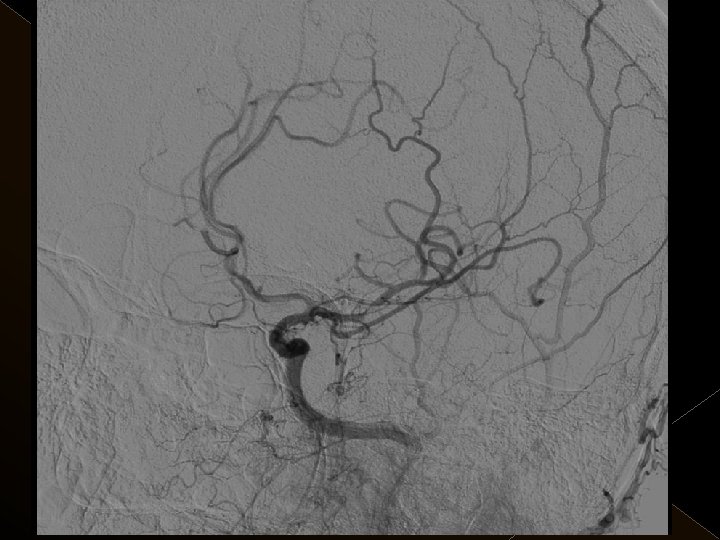

� 25 hasta (16 K, 9 E) , 27 vaskuler okluzyon � 16 orta serebral arter (MCA), � 6 baziler arter ve � 5 internal karotis arter (İCA) düzeyinde olmak üzere � Toplam 25 hasta, 27 tıkanıklığa (6 sı hariç) iv tpa sonrası endovaskuler yolla müdahale edildi

Acil servise başvuru süreleri: 1 -4. 5 saat Başvuru sırasındaki ortalama NIHSS skoru: 23 25 hastanın 21’inda kontrol serebral anjiografide tıkanıklığın tamamen açılmış olduğu görüldü. � Baziler arter ve ICA tıkanıklığı olan 4 hasta kaybedildi. � 19 hastanın 16’sında NIHSS skorlarında işlem sonrasında 24. saatte yapılan klinik değerlendirmede ortalama 10 puanlık düşüş saptandı. � � �

� İnme tedavisinde iv tpa uygulamasını takiben � intraarteriyel (İA) trombolitik tedavi (ia tpa ve ia mekanik trombolizis) � İA stent yardımı ile trombektomi yöntemleri kullanılarak tedaviye cevap ve komplikasyonlar araştırıldı.